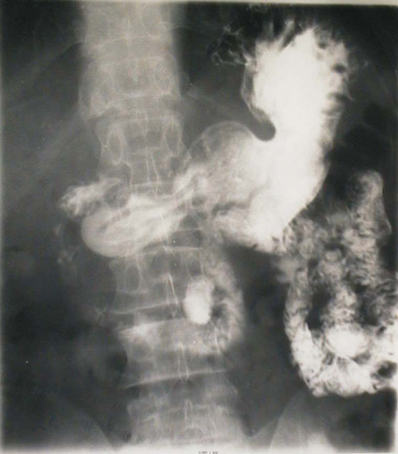

| Diverticules de l'intestin .

Image de trois diveticule le long de l'intestin se

voyait si net sur cliche de face du transit baryte

avec tech compression dose de l'abdomen . |